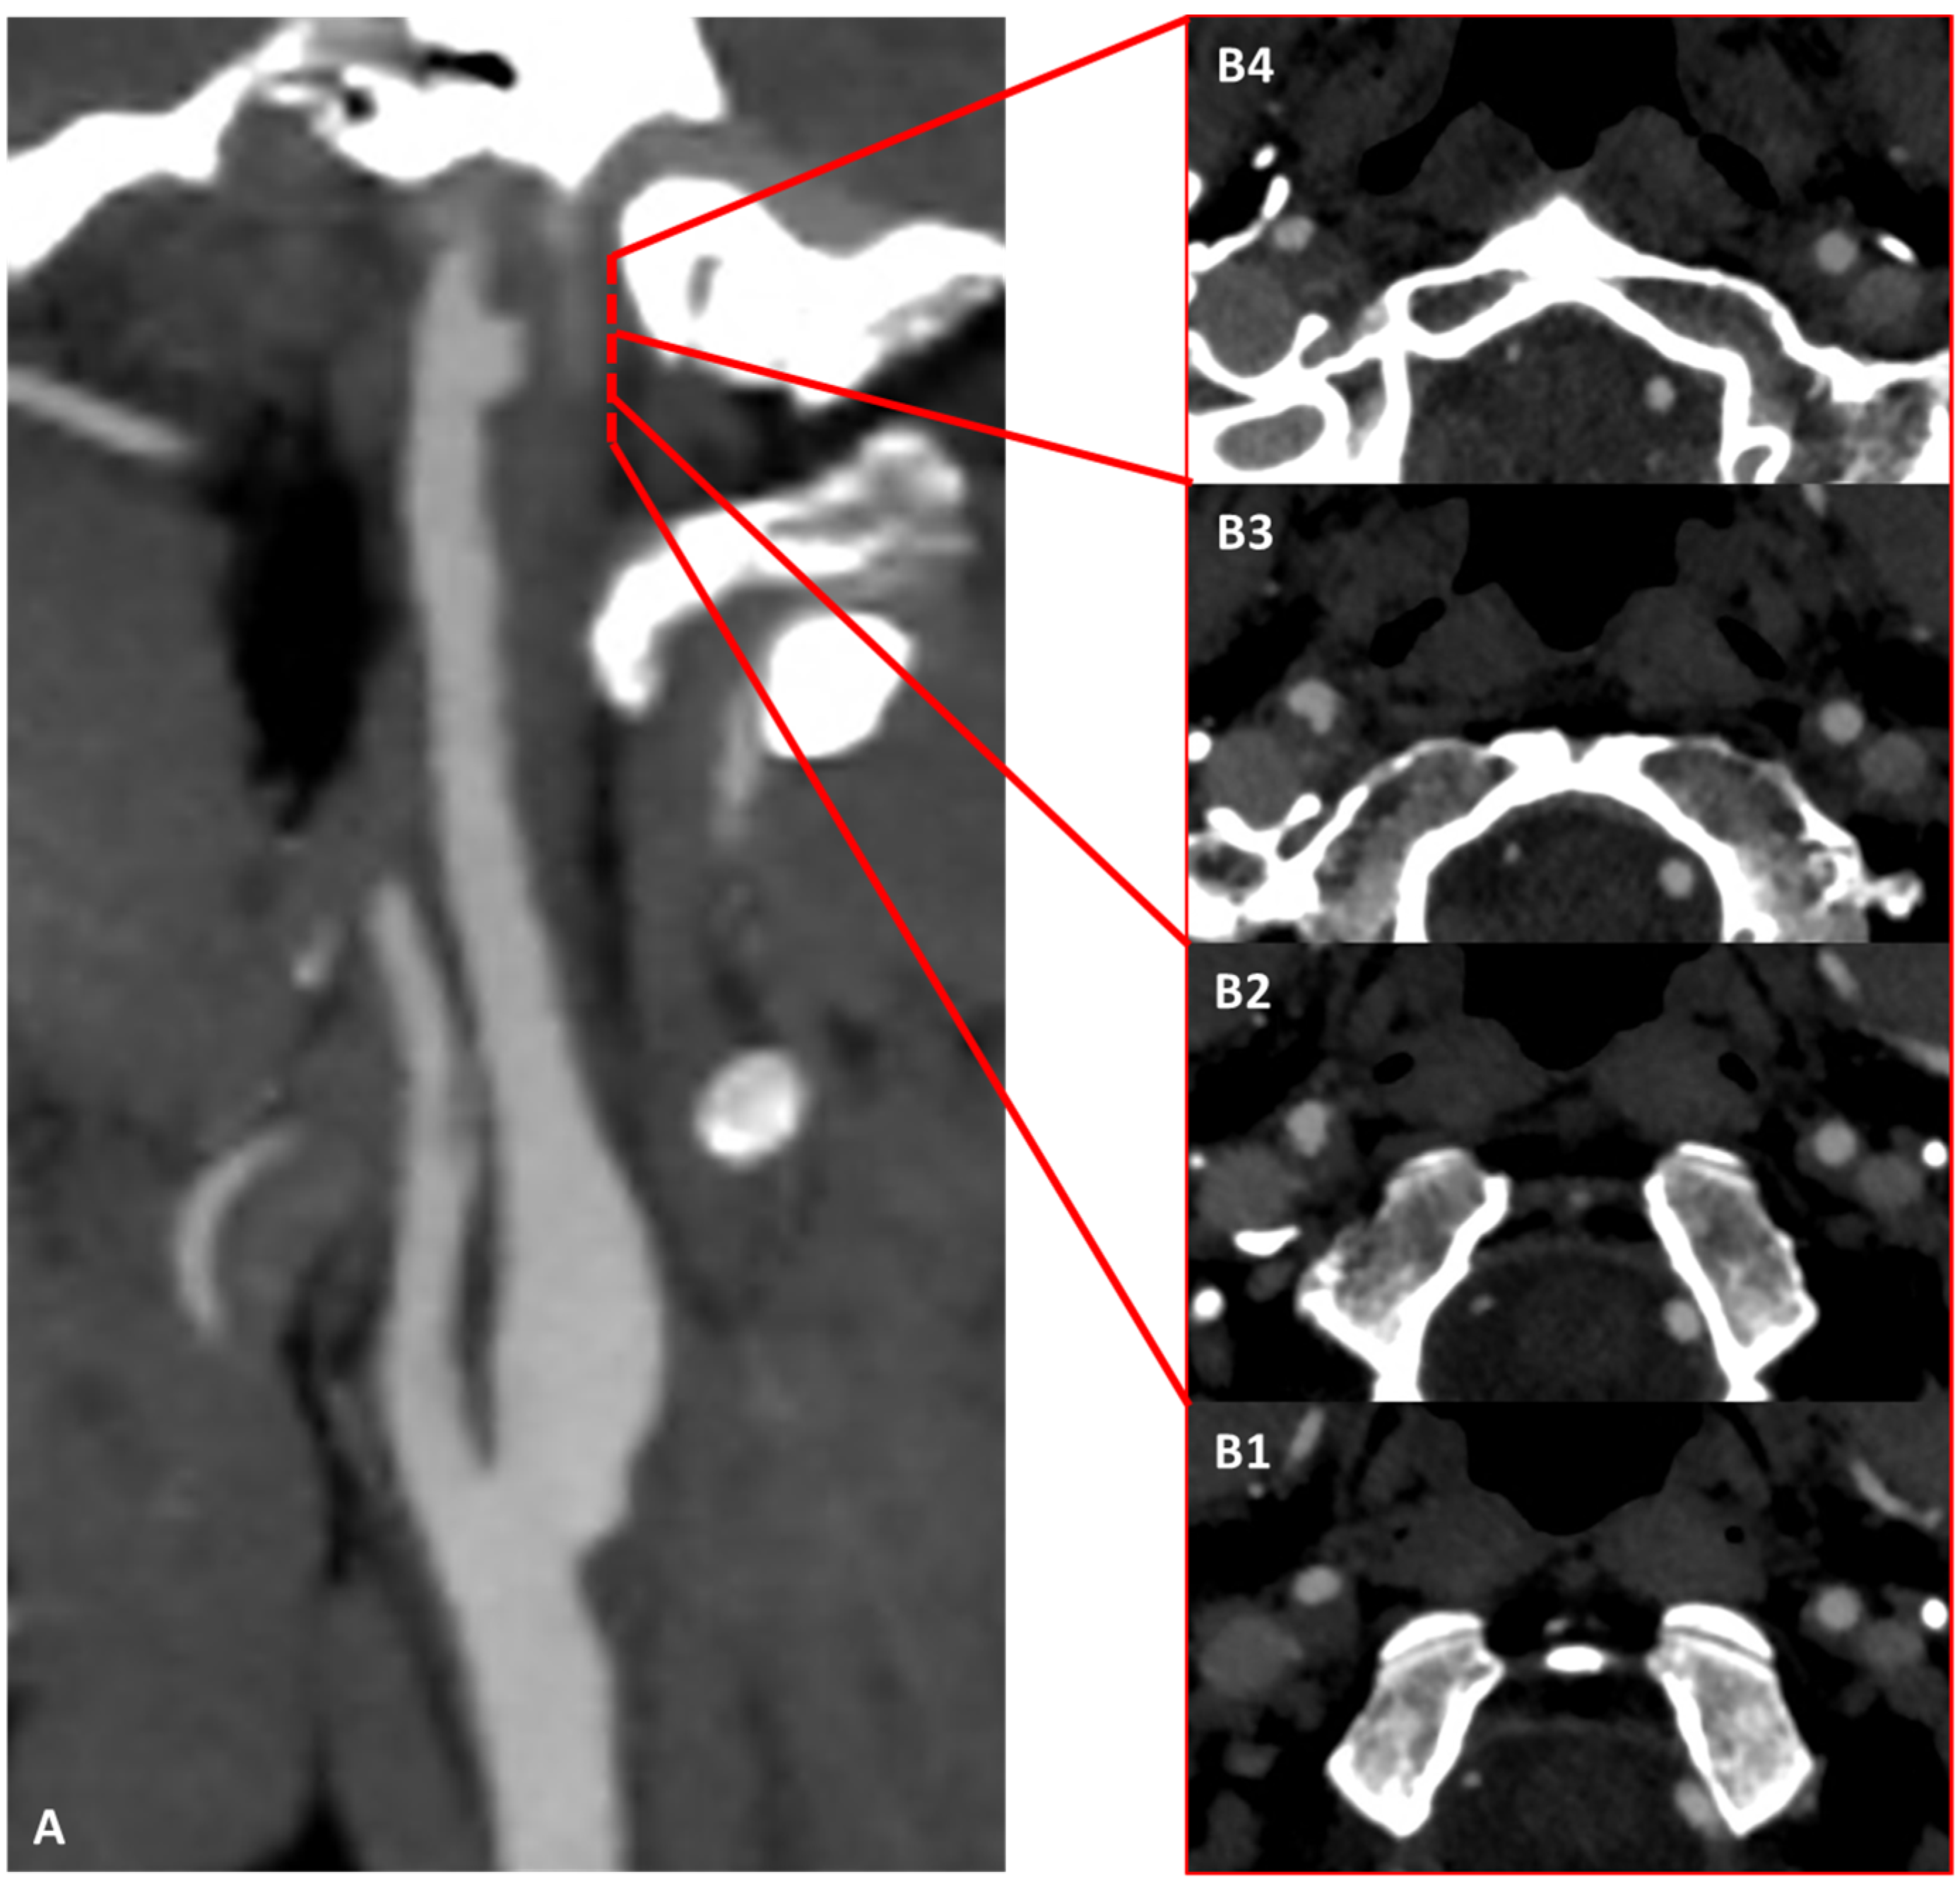

3.1. Case 1

3.2. Case 2